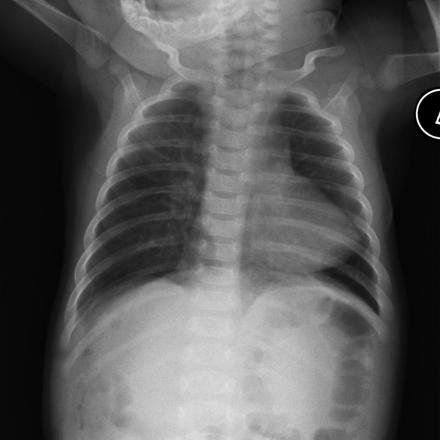

- Chest radiograph may show “boot shaped heart” and right aortic knob

“boot shaped heart” Case courtesy of A.Prof Frank Gaillard, Radiopaedia.org. From the case rID: 8049